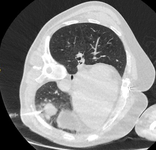

Computed tomography (CT) showing examples of malignant perifissural nodules. Note the spiculated edge of the nodules and the evident retraction of the adjacent fissure. Both resection tissue analyses confirmed adenocarcinoma of lung

From the collection of Dr George Tsaknis, MD, PhD, FRCP(London), MRQA, MAcadMEd, PGCert; used with permission